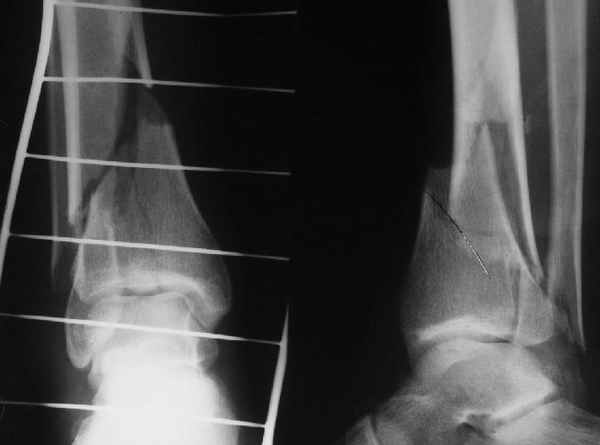

Да и нет! Зависит от перелома и способа остеосинтеза. А результат? (01)

Кликните для загрузки файла 01.jpg

65KB (66785 bytes)

Мы же говорили о проксимальном плече. При переломе tibia, конечно, речи о двух Y-спицах нет. Еще раз о них - пружинящая подвижность без "срезающих" перемещений фрагментов - дополнительный стимул к образованию периостальной мозоли.

А в данном случае - у нас был бы применен locked nail с еще меньшими дырочками на коже и с возможностью полной нагрузки немедленно после операции. Какие тут аргументы в пользу выбора пластины, а не интрамедуллярного гвоздя?

Классически показанием для locked nail яв-ся зоны BC CD, до появления LCP показания к locked nail несколько расширялись в зоны AB и DE

Аргументы: перелом достаточно низкий, трудно будет ввести 3-и блок. винта, а учитывая характер перелома на 2-х дистальных винтах я бы не рекомендовал немедленную полную нагрузку.